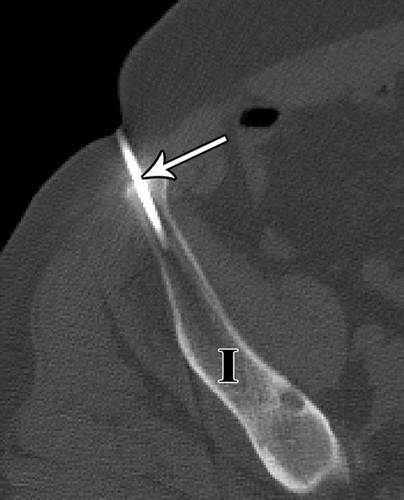

16 - 55岁的妇女转移性乳腺癌。椎弓根溶解病变(箭头)使用经椎弓根方法。

典型地,使用通过椎弓根的方法对椎体损伤进行活组织检查(图16))。然而,如果病变的震中不能通过椎弓根进入,可考虑腰椎椎间盘入路(图17)。向软组织中注射盐水可以用于使组织远离脊柱移位,并使相邻的肺远离针的路径(图18A,18B)。